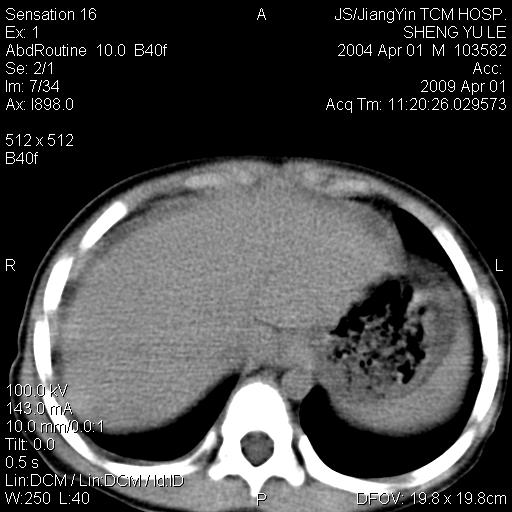

m,5岁。尿痛尿频数天。既往无病史。ct平扫腹盆腔积液。膀胱壁明显增厚。另可见心包增厚。wbc5万,骨髓穿等结果。请指教。

膀胱影像表现结合临床应该是急性膀胱炎症,但为什么有腹水呢?双肾输尿管无扩张,泌尿系压力应该不大不至于引起尿外渗,应该是腹膜感染引起的,但楼主没有提及相关症状,腹膜及膀胱结核?患者白细胞5万(结核不至于这么高啊),脾脏增大,是不是有白血病?进一步检查。。